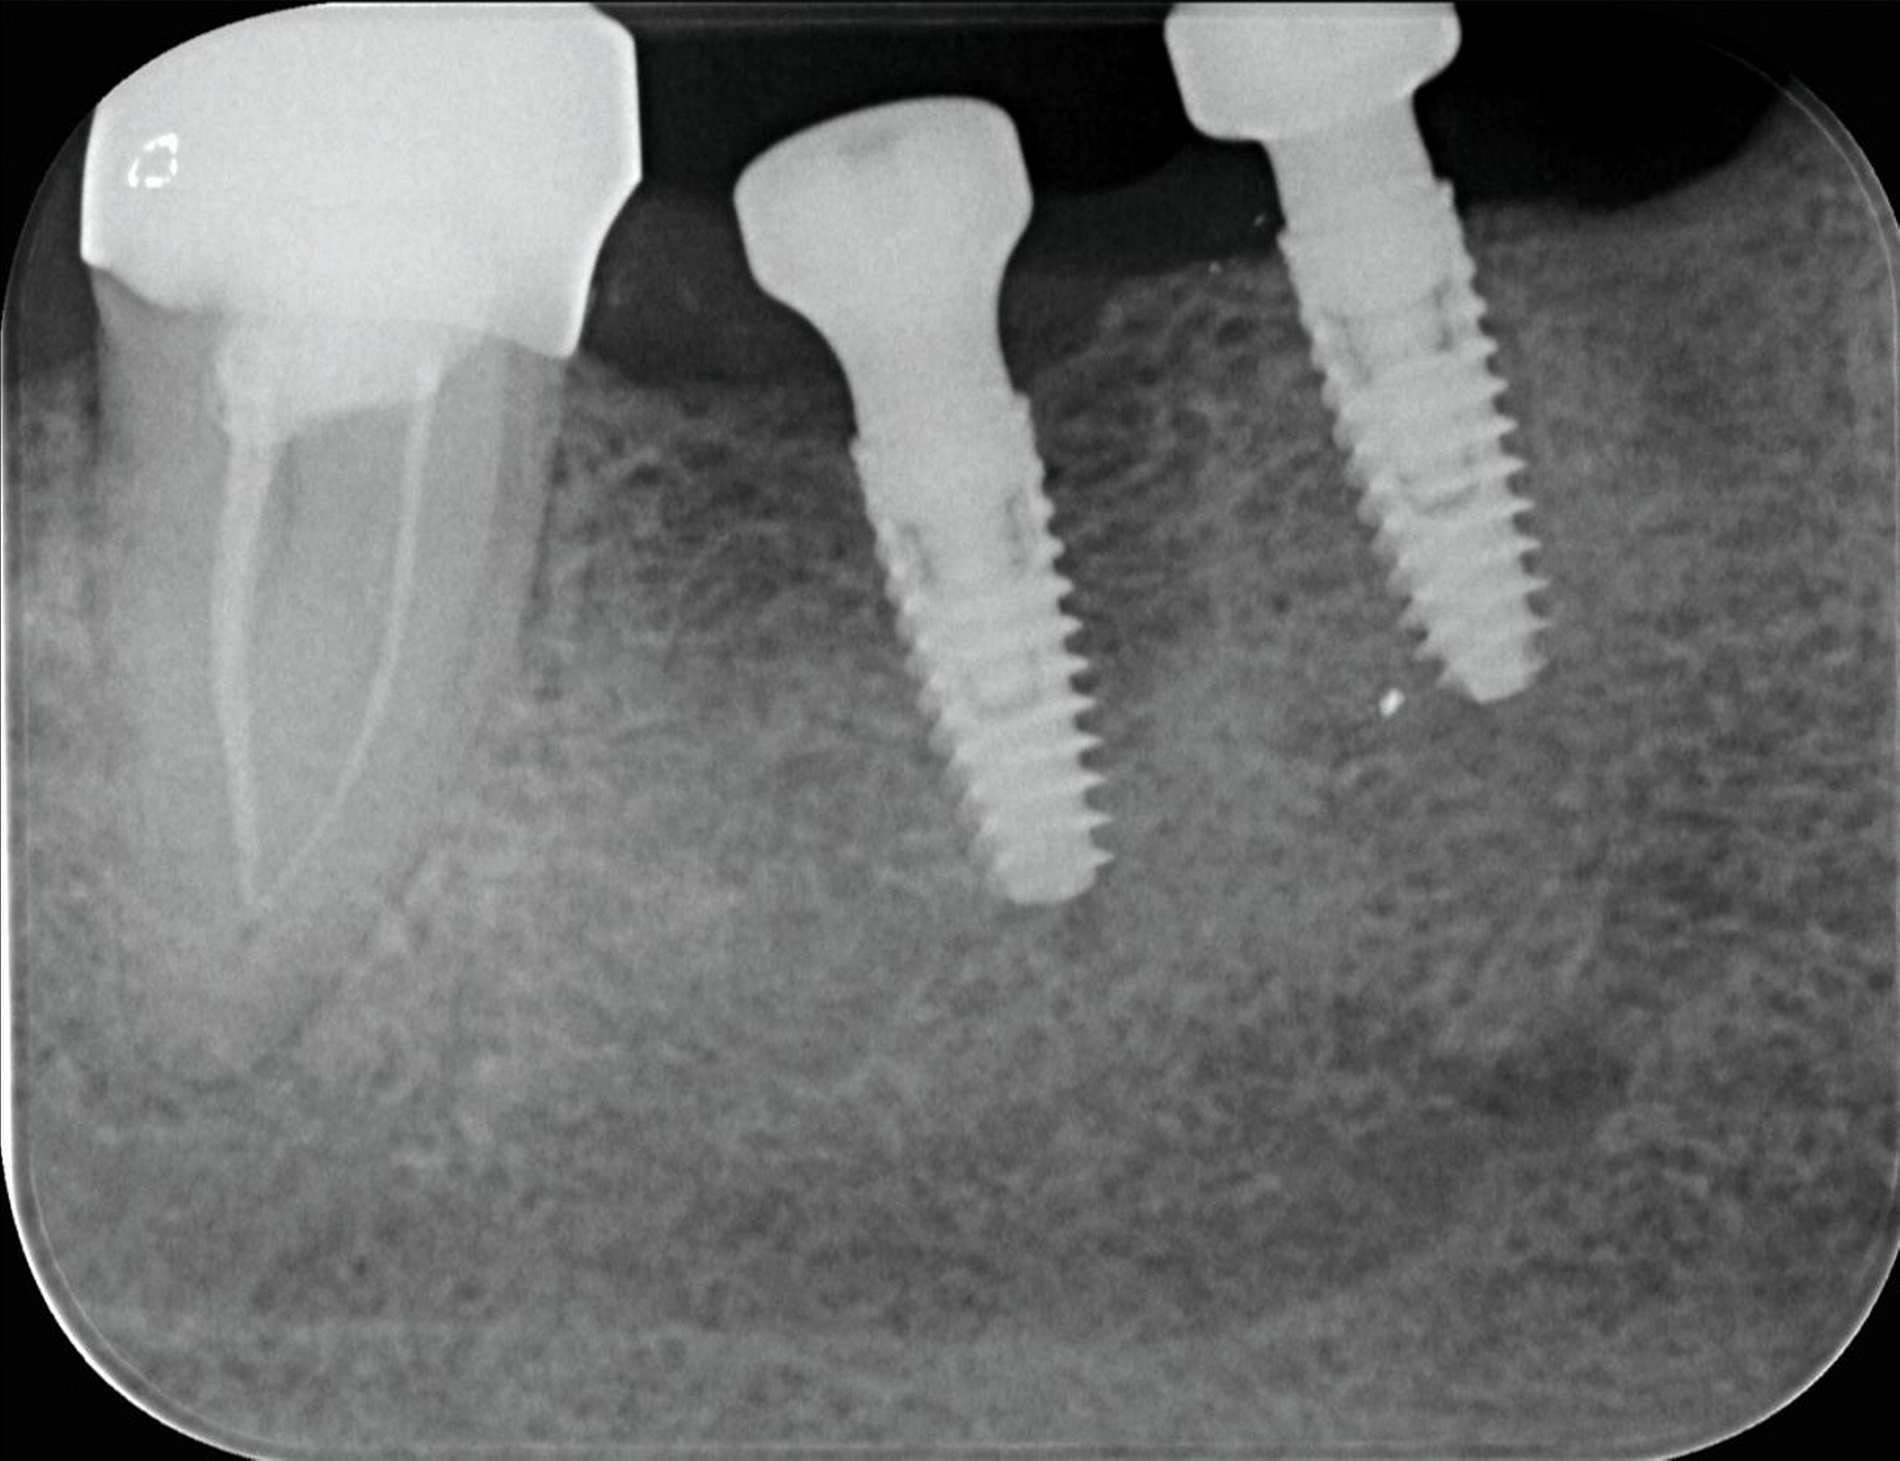

Das herstellerseitig empfohlene Vorgehen sieht vor, das Abutmentfragment zentral mit einem runden Bohrer oder Diamanten (Ø 1,2–1,4 mm) anzukörnen. Anschließend erfolgt die Bohrung mit einem speziellen Kernlochbohrer (Ø 1,8 mm, Tiefe circa 3 mm) bei 1800 U/min und unter Kühlung. Ein passender Extraktionsstift wird eingeschraubt und das Schraubenfragment mithilfe eines Ausdrehers entfernt. Für verbliebene Gewindehülsen stehen spezielle Ausdrehinstrumente zur Verfügung; in schwierigeren Fällen kann zusätzlich ein Spiralbohrer (1,4 mm) zum Einsatz kommen. Der finale Schritt besteht in der Nachbearbeitung des Innengewindes mit einem Gewindeschneider (M1,8). Zur Minimierung des Friktionswiderstands kann die Verwendung eines Gleitmittels (zum Beispiel Vaseline) hilfreich sein. Ein verkantungsfreies Arbeiten ist essenziell, um Instrumentenbruch und Implantatverlust zu vermeiden. Die radiologische Darstellung des Bruchs sowie die Situation nach Entfernung der Komponenten sind in den Abbildungen 3 und 4 dokumentiert.